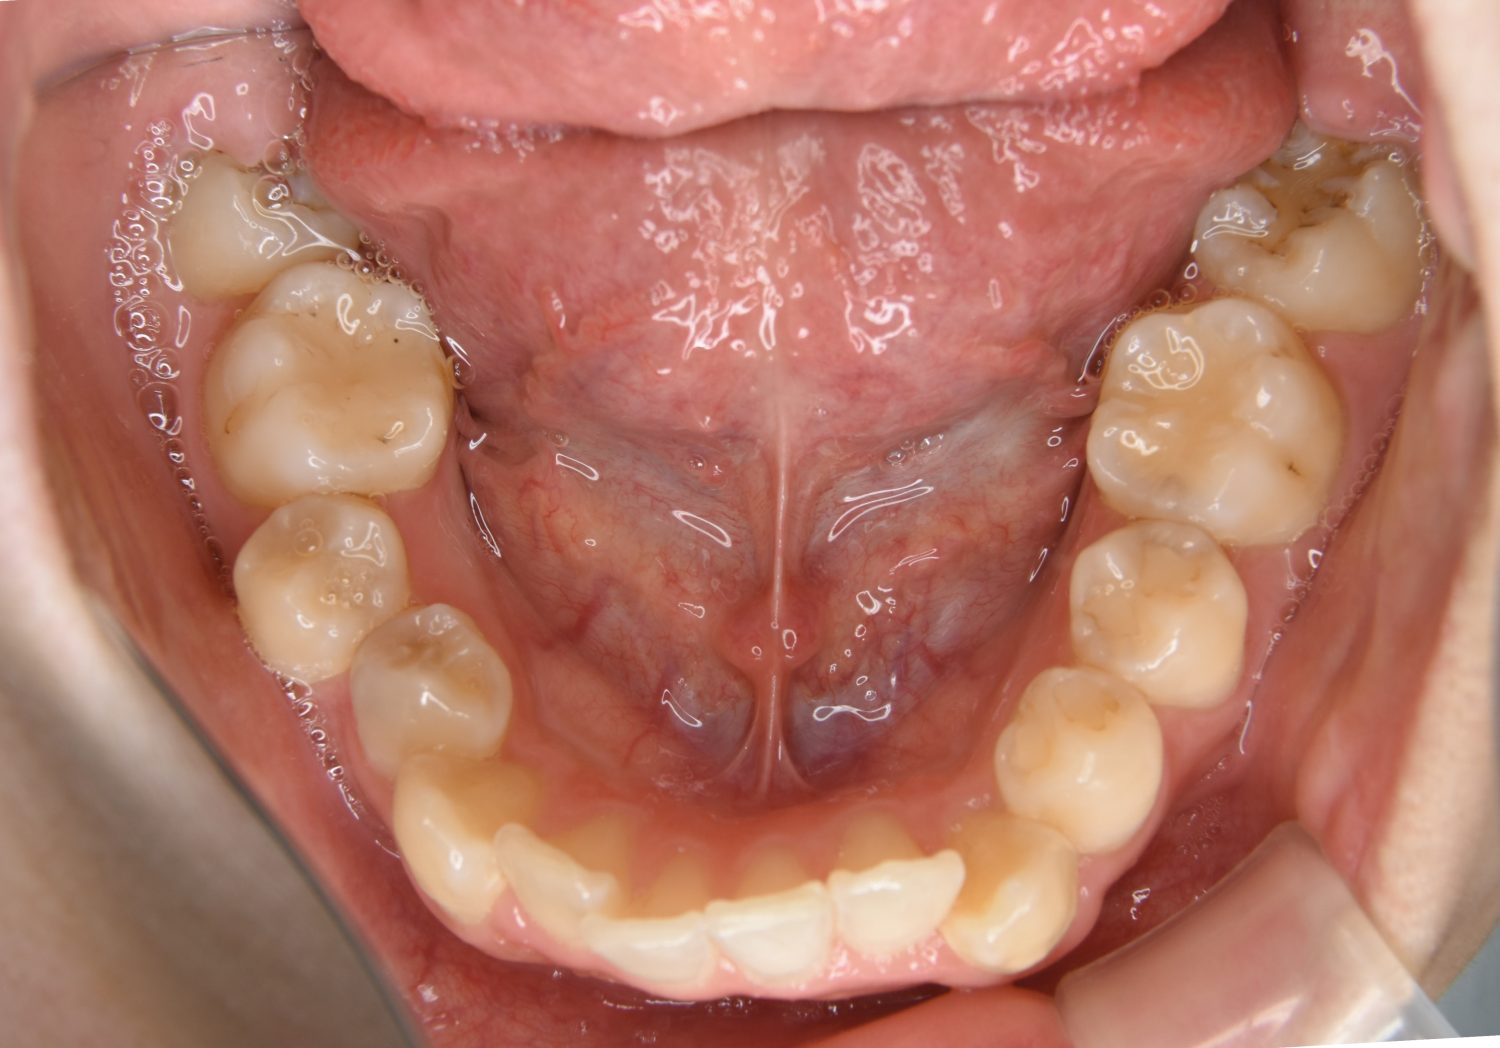

叢生の症例紹介②

Before

After

主訴

歯の凸凹を治したい。

治療内容

アライナー(インビザライン)にて非抜歯で治療を行いました。

治療費

1,150,000 円(税込)

治療期間

26ヶ月

通院回数

14回

想定されたリスク

※歯根吸収、歯肉退縮、歯髄壊死、顎関節症状

※アライナー(インビザライン)は日本の薬機法未承認の矯正装置であり、医薬品副作用被害救済制度の対象外となる場合があります。

丸山和宏先生

ピーススマイル矯正歯科

上下前歯部に叢生(凸凹)が認められる状態でした。歯列の遠心移動を行うことで機能面および審美面が改善されました。